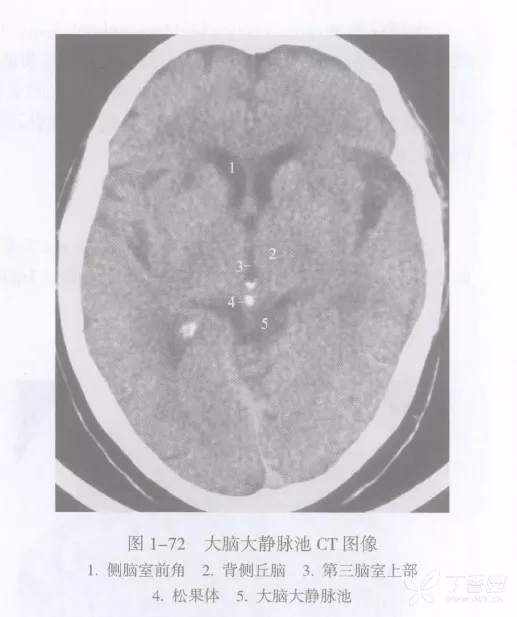

大脑大静脉池

大脑大静脉池 Galen's vein cistern 是四叠体池向上的延续,居第三脑室的后方,上抵胼胝体压部。池内前有松果体,后有大脑大静脉。

在CT 图像上,大脑大静脉池在第三脑室上部与“V” 型小脑幕影之间,与第三脑室上部共同显示为菱形低密度区。池内的松果体易于显影,如钙化则更为明显,而大脑大静脉须强化后才能看到。